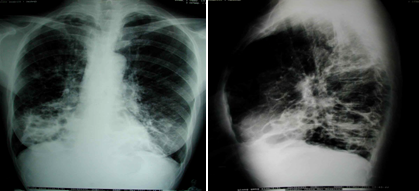

①胸部X线片

粗乱

支气管柱状扩张典型的表现是轨道征,为增厚的支气管壁影。

囊状扩张特征性改变为卷发样阴影,表现为粗乱肺纹理中有多个不规则的蜂窝状透亮阴影。